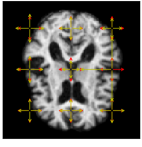

Refer to caption

Figure 4: From left: (1.) Pixel-wise variation in the data. (2.) Variation estimated by the model. (3.) Estimates of the variance parameter τk2superscriptsubscript𝜏𝑘2\tau_{k}^{2} compaired to the true values (4.) Estimates of the variance and amplitude parameter compaired to the true values. The length of the arrows correspond to τkλksubscript𝜏𝑘subscript𝜆𝑘\tau_{k}\lambda_{k}. The arrows show the location and width of the noise fields. The red arrows correspond to the true values, while the yellow defines the resulting estimated parameters.

Fig. 4 shows the initial brain, I0subscript𝐼0I_{0}, with a comparison of the true values of τksubscript𝜏𝑘\tau_{k} and λksubscript𝜆𝑘\lambda_{k}, and the values found by the optimisation procedure. The red arrows are the true values, and the yellow defines the estimated parameter values. The model is able to retrieve the parameters of τksubscript𝜏𝑘\tau_{k} for all k=1,,9𝑘19k=1,\ldots,9. It also returns a good estimate of the amplitude parameters, in particular for the noise fields located inside the brain. For noise fields on the boundary of the brain or in the background, the model does not have access to enough information in the intensity differences to return precise estimates of the amplitude parameters.